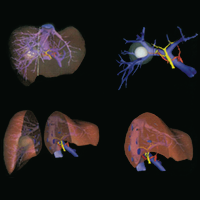

Preoperative hepatic 3D models: virtual liver resection using three-dimensional imaging technique (2005)

Numminen, Kirsti and Sipilä, Outi and Mäkisalo, Heikki

European journal of radiology, vol. 56 (2): 179–184